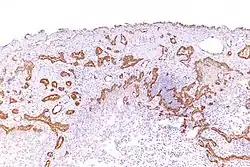

Mesothelioma

Using immunohistochemistry, calretinin can be demonstrated in both benign mesothelium and in malignant mesothelioma[12][13] and can be used to help differentiate different lung tumours.[14] Antibodies to calretinin can also be used to distinguish between different types of brain tumour, demonstrating only those with neuronal rather than glial, differentiation.[15] Furthermore, the essential function of calretinin in mesothelioma cell lines has been demonstrated in vitro and may be an interesting target for therapeutical approaches.[16]